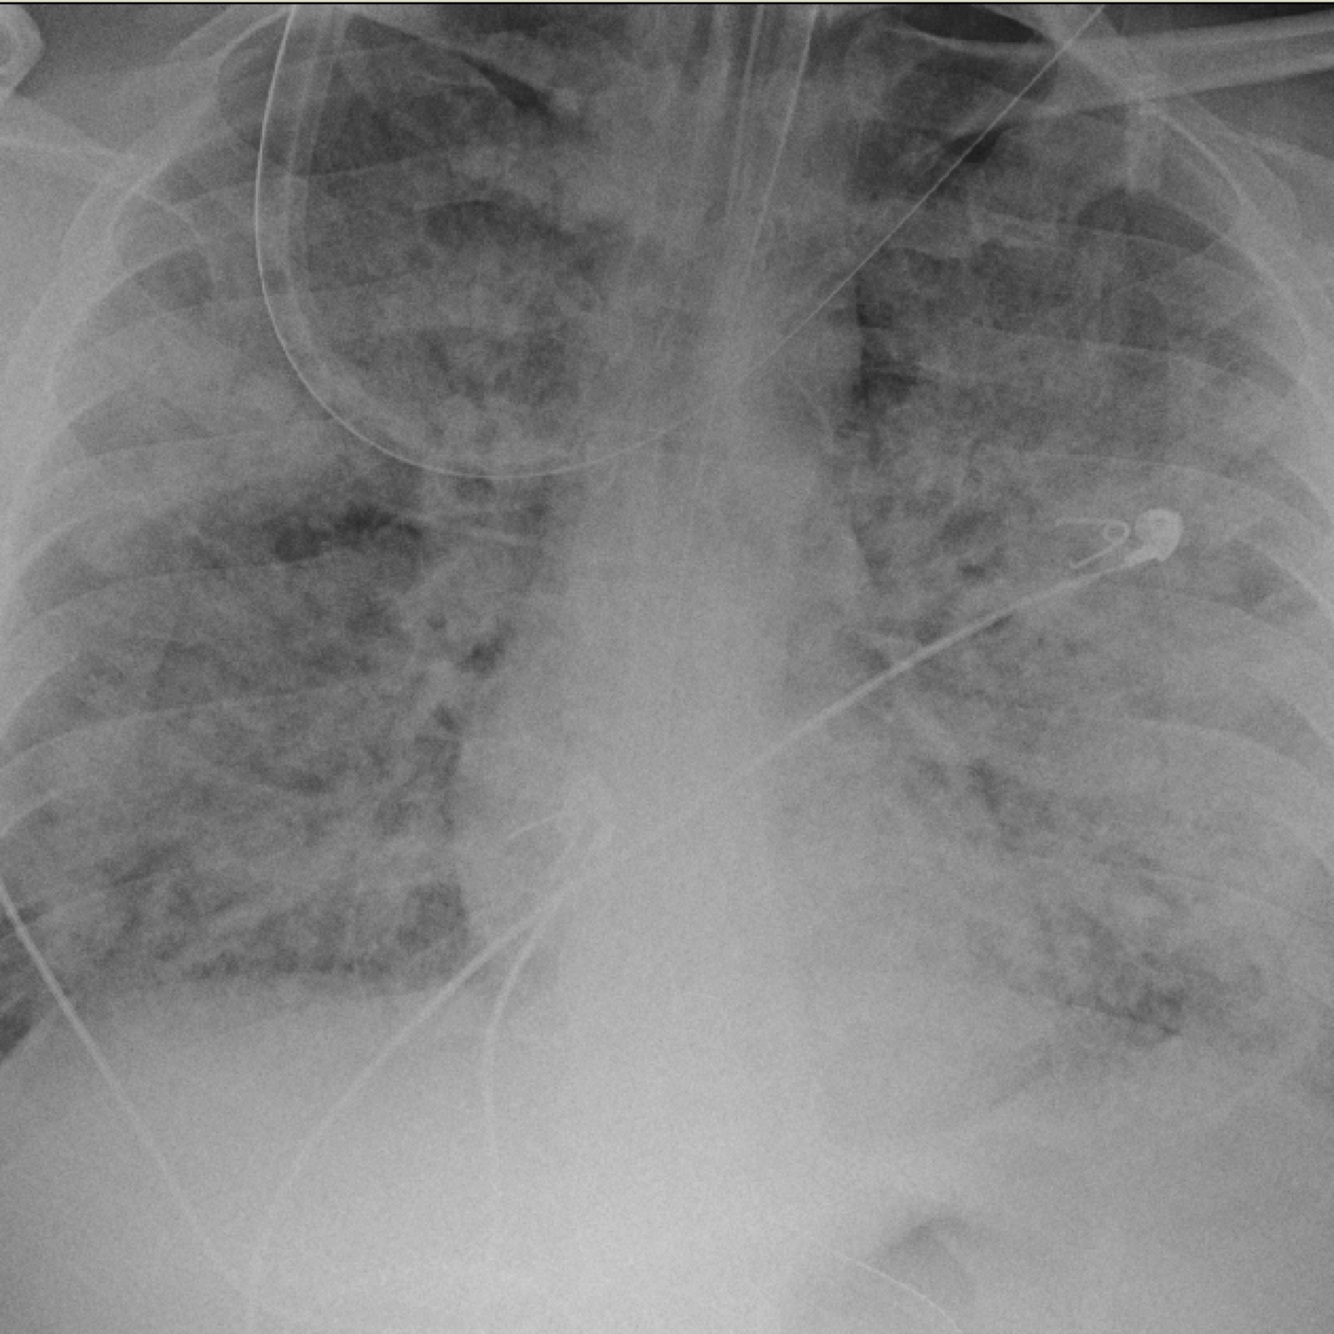

Achado radiográfico da SDRA

Infiltrado pulmonar bilateral (edema pulmonar)

Aspecto da SDRA na TC de tórax

Consolidações posteriores e opacidade difusa bilateral

Critérios de Berlim (2012) para diagnóstico da SDRA

• infiltrado bilateral à imagem